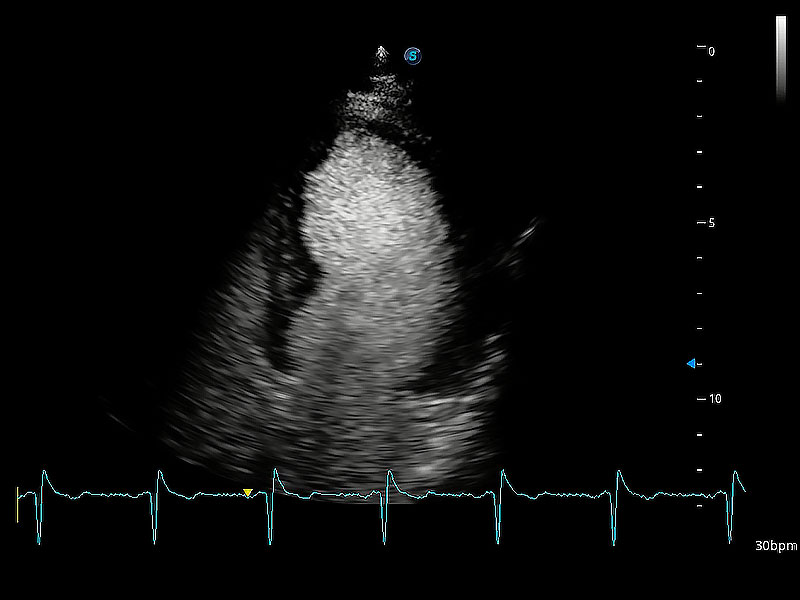

ProPet 80 配备了丰富的心脏探头群、先进的成像技术和专业的心脏测量工具,可帮助动物医生为不同体型和生理结构的动物提供心脏和心肌功能的全面评估。